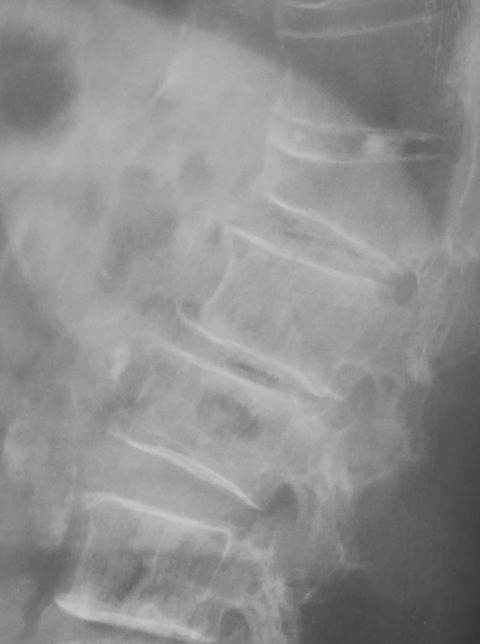

この患者さんは、骨粗鬆症が高度のためにいくつかの脊椎に圧迫骨折を併発しています。見た目にも円背であり、脊椎アライメントは著明な後弯変形しています。

今回のように脊椎圧迫骨折のためにアライメントが変わってしまった患者さんには、逆流性食道炎や失禁などを併発することがあります。